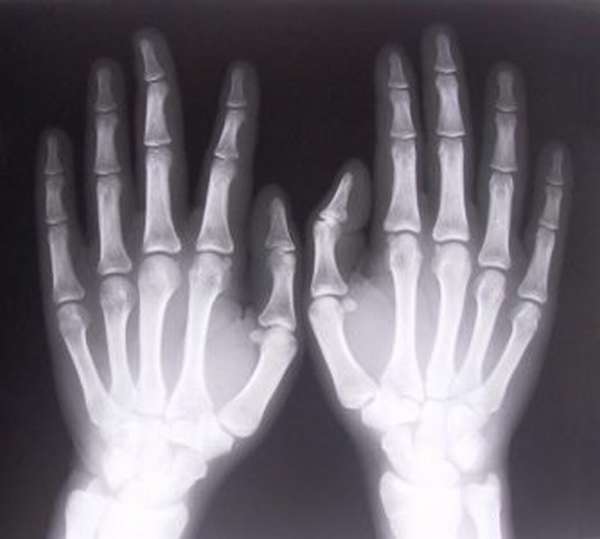

Рентгенография вывиха пальца руки

С целью диагностики проводится рентгенография, которая в полной мере позволяет оценить тип и выраженность травмы. В отдельных случаях дополнительно назначается КТ или МРТ.

Обычно достаточно рентгена (желательно цифрового). Если он не дает полной картины повреждения, то нужно делать компьютерную или магнитно-резонансную томографию.

Для окончательного диагноза понадобится рентген. Обычно его делают в двух или трех проекциях. Рентгенография позволяет точно определить патологические изменения в кисти.

Для подтверждения диагноза необходимо выполнить рентгенограмму пальцев кисти в двух проекциях. Если есть подозрения, что у пациента возможен отрыв сухожилья его могут отправить на компьютерную томографию.